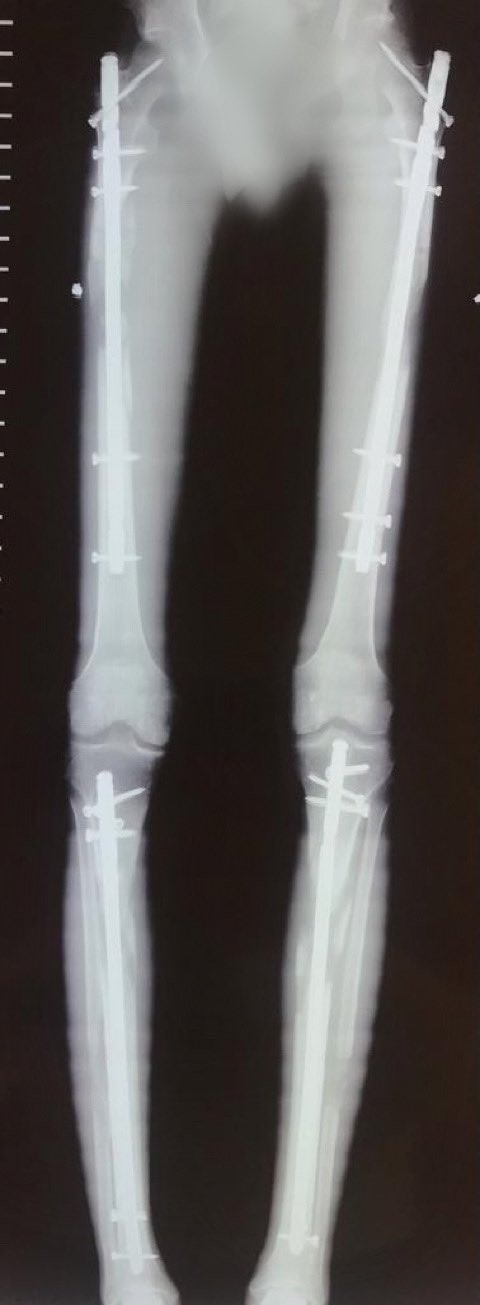

骨延長手術を受けた157センチの男性、無事169センチの長身の身体を手に入れる